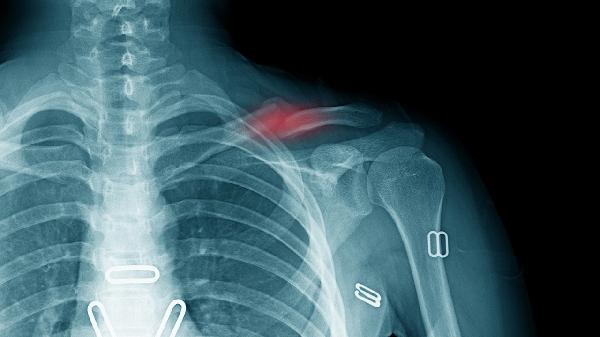

术后4周X线显示连续骨痂形成是安全活动的关键指标。CT三维重建能更准确判断愈合情况。医生触诊确认骨折端无异常活动后,方可逐步进行梳洗动作,从低位扎马尾开始适应。